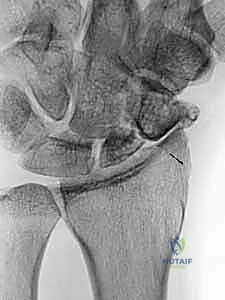

لا تُكتفى بصورة أشعة عادية، بل يتم طلب "مناظر العظم الزورقي الخاصة" (Scaphoid Views) بوضعيات محددة لليد (مثل الانحراف الزندي - Ulnar Deviation) لإبراز العظم الزورقي بوضوح. تُظهر الأشعة السينية وجود الفجوة، التصلب العظمي (Sclerosis)، أو التكيسات التي تدل على عدم الالتحام.

التصوير المقطعي المحوسب (CT Scan)

يُعد التصوير المقطعي المعيار الذهبي (Gold Standard) لتأكيد عدم التحام العظم الزورقي وتقييم التشوه الهندسي للعظم. يوفر الـ CT Scan صوراً ثلاثية الأبعاد دقيقة للغاية توضح حجم الفجوة العظمية، درجة زاوية التشوه (Humpback Deformity)، ومقدار العظم المفقود، مما يساعد الدكتور هطيف في التخطيط الدقيق لحجم الطعم العظمي المطلوب.

التصوير بالرنين المغناطيسي (MRI)

يتم اللجوء للرنين المغناطيسي لسبب رئيسي واحد: تقييم التروية الدموية وتأكيد وجود النخر اللاوعائي (AVN). إذا أظهر الرنين المغناطيسي أن الجزء القريب من العظم الزورقي داكن ولا يمتص الصبغة، فهذا دليل قاطع على موت العظم. في هذه الحالة، يصبح "ترقيع العظم الوعائي الظهري" هو الخيار الجراحي الوحيد الفعال، حيث أن الطعوم العظمية التقليدية ستفشل حتماً.